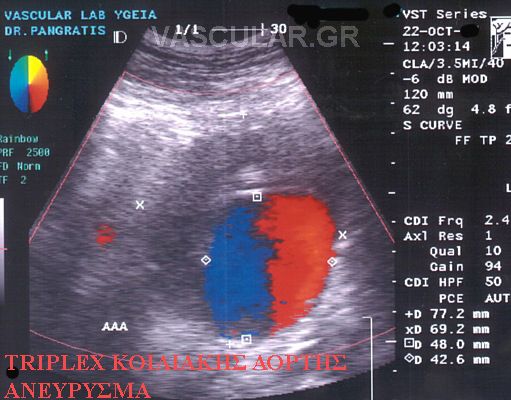

ÓõíÞèùò ç äéÜãíùóç ôïõ áíåõñýóìáôïò ãßíåôáé ôõ÷áßá ìåôÜ áðü êÜðïéá äéáãíùóôéêÞ åîÝôáóç üðùò áêôéíïãñáößá óôçí êïéëéÜ, áîïíéêÞ Þ ìáãíçôéêÞ ôïìïãñáößá êïéëßáò êáé êõñßùò áðü õðåñç÷ïãñÜöçìá Triplex , åéäéêüôåñá äå ìåôÜ áðü áããåéïãñáößá Þ õðåñç÷çôéêÞ ðáíáñôçñéïãñáößá.

Õðåñç÷çôéêüò Ýëåã÷ïò triplex åðéâÜëëåôáé óå üëïõò ôïõò áóèåíåßò ðïõ ðáñïõóéÜæïõí éóôïñéêü, ìå éó÷áéìéêÜ óõìðôþìáôá Þ êëéíéêÜ åõñÞìáôá éó÷áéìßáò Üêñùí êáé ïñãÜíùí, êáñùôéäéêÞ óôÝíùóç óõìðôùìáôéêÞ – áóõìðôùìáôéêÞ, õðÝñôáóç Þ óôåöáíéáßá ðÜèçóç, éó÷áéìßá êÜôù Üêñùí êáé ýðáñîç óõããåíïýò ðñþôïõ âáèìïý ìå áíåýñõóìá ôçò êïéëéáêÞò áïñôÞò (ÁÊÁ).